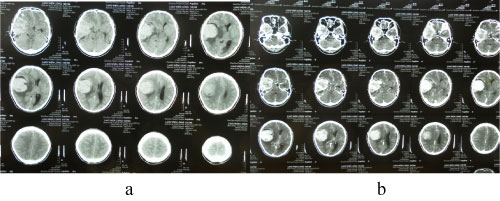

A 34-year-old man presented to hospital in 2006 with headache, tinnitus, intermittent nausea for one months. Cranial computed tomography (CT) demonstrated the right sphenoid ridge lesions (Figure 4), and underwent surgical excision of the right sphenoid ridge tumor under general anesthesia (Figure 5). Meningioma was diagnosed post surgically. In 2010, a following up computed tomography of the patient revealed a small recurrence of meningeal tumor and then treated with Gamma knife (Figure 6 and Figure 7).

Figure 6: The cranial CT test before the Gamma knife therapy (2010). View Figure 6

Figure 7: CT after the Gamma knife therapy (2010). View Figure 7